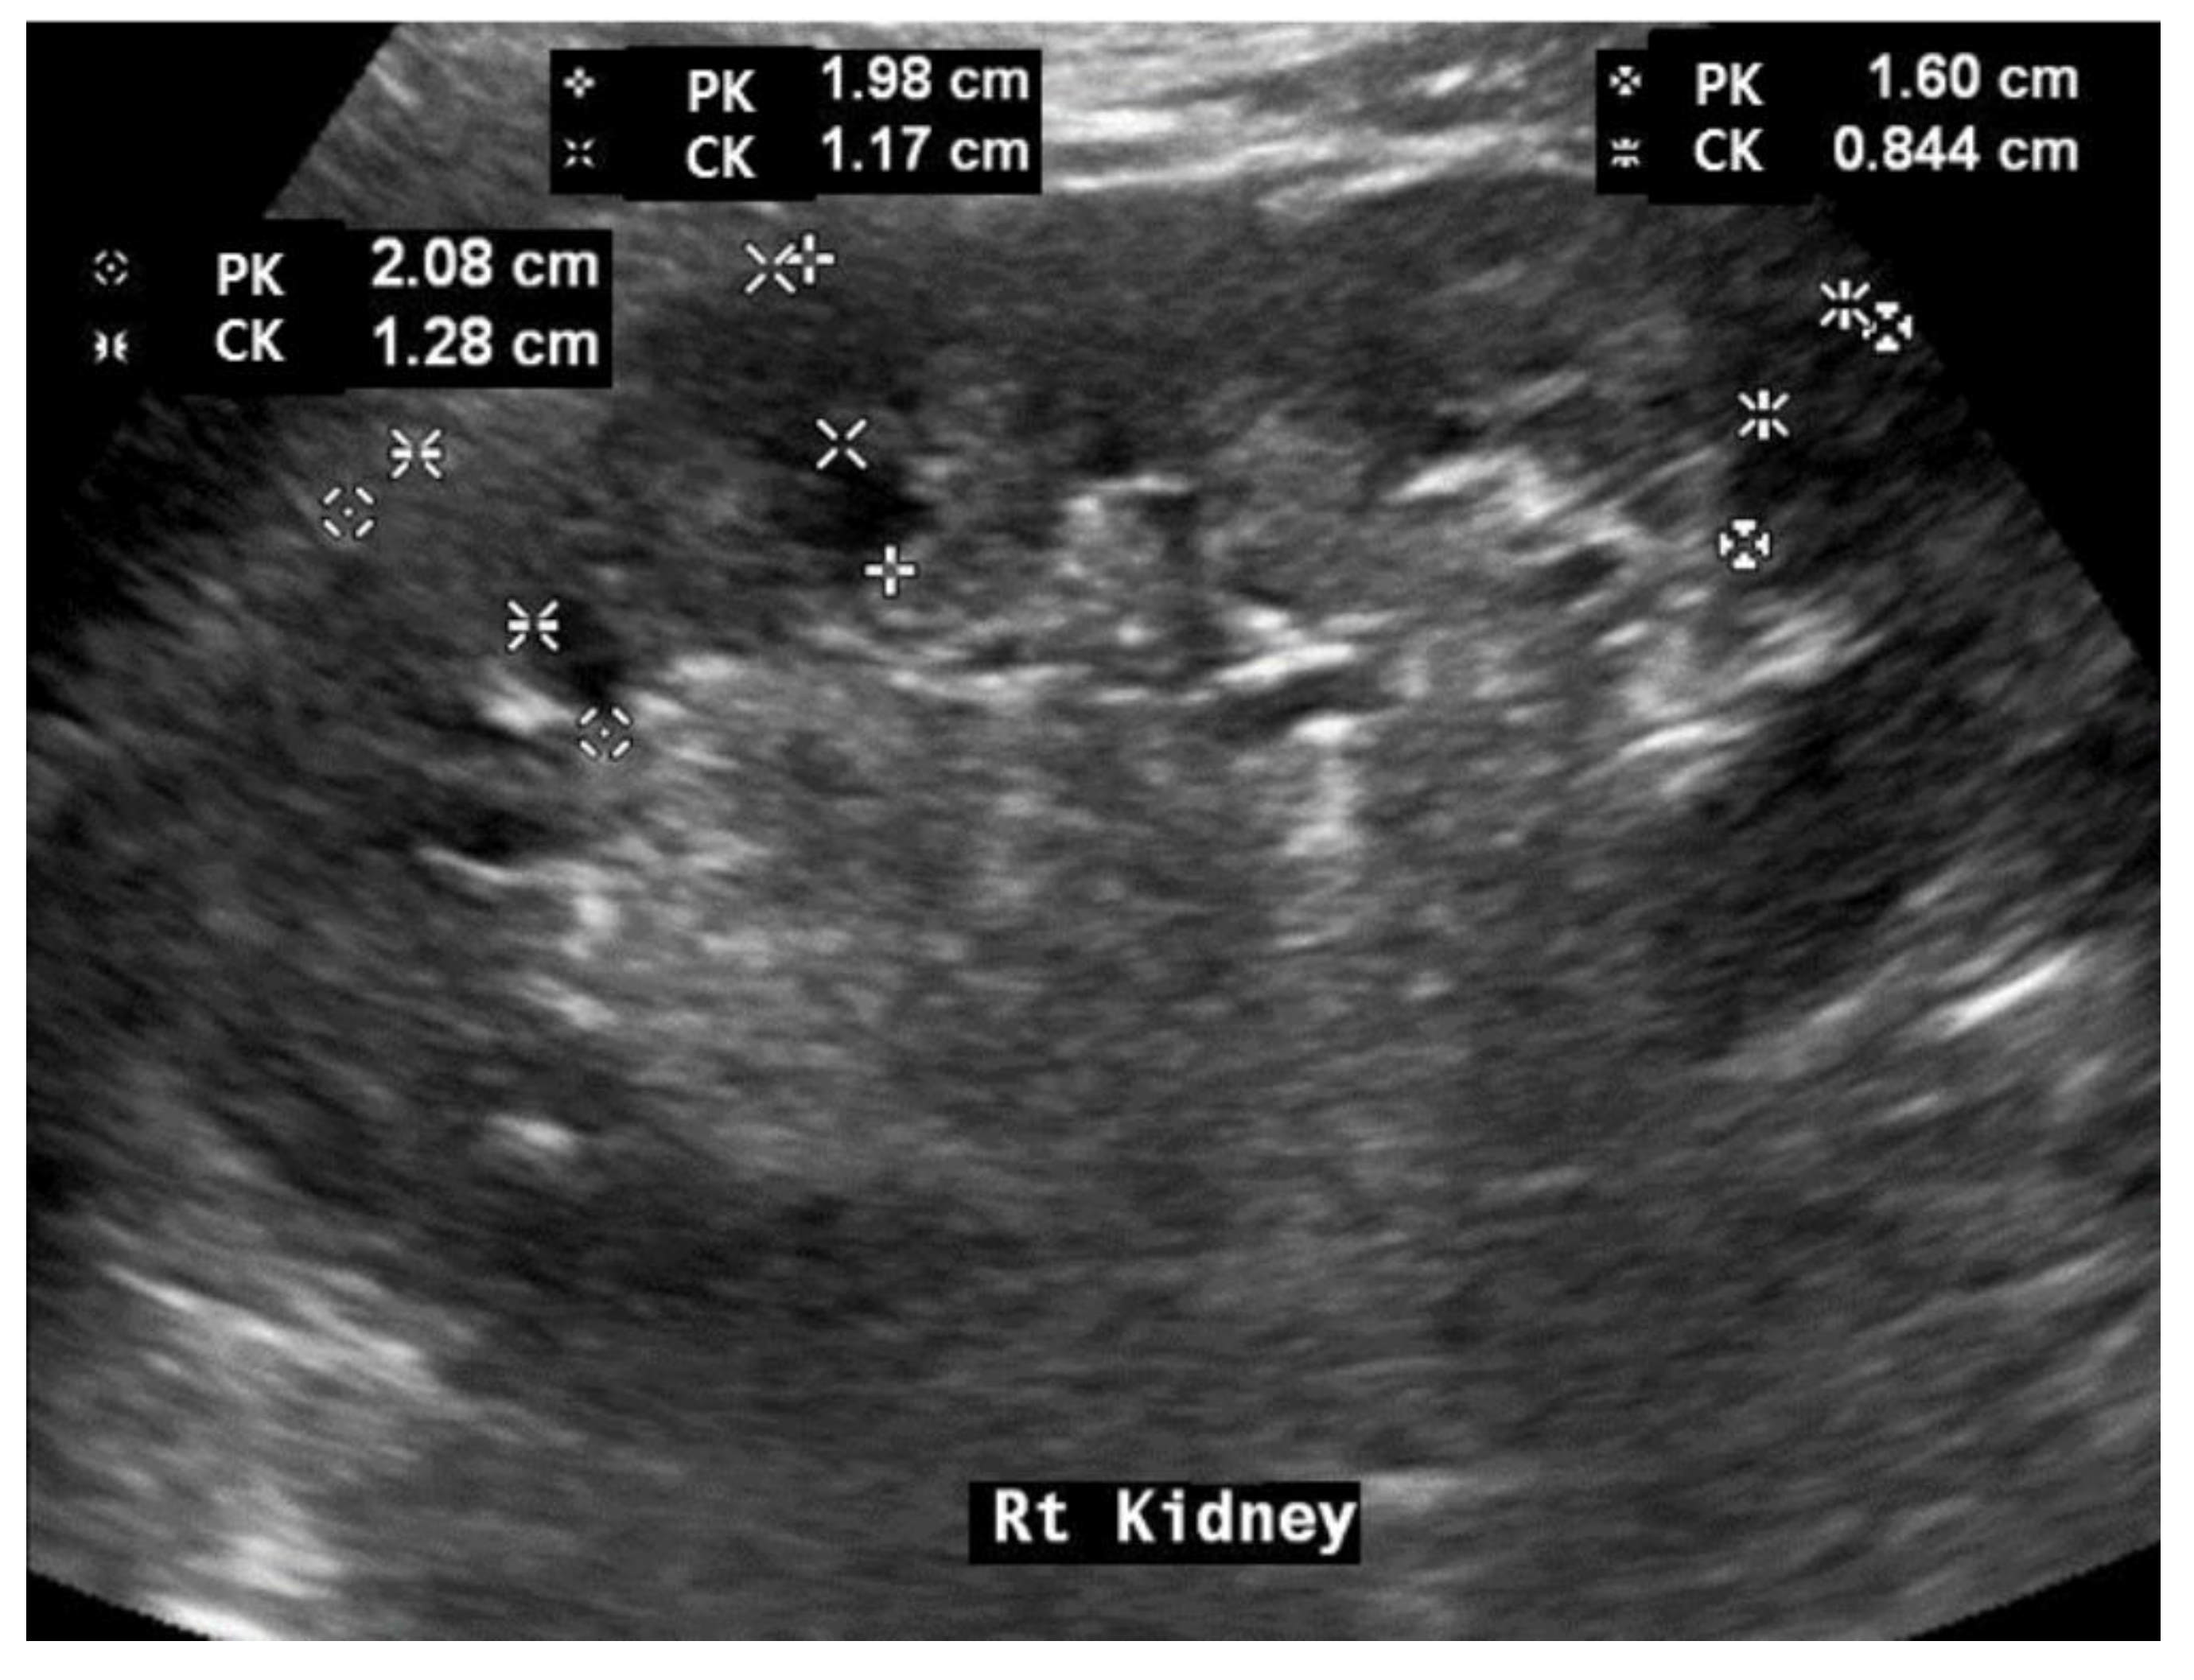

2.4. Renal Ultrasonography Examinations

| Value | Scoring | Value | Scoring | |

|---|---|---|---|---|

| RK (cm) | 11.6 | Height (m) | 1.698 | |

| CK (cm) | 1.1 | PK (cm) | 1.89 | |

| RH: RK/Height | 6.83 (Median: 6.427) | CKH, 10 × CK (RH) | 1.61 (Median: 0.99) | |

| value | Scoring | |||

| Echogenicity | Normal (0) | Slightly increased (1) | Increased (2) | 0 |

| Capsular irregularity | Normal (0) | Slightly irregular (1) | Irregular (2) | 0 |

| CK/PK | Above (0) | Median | Below (1) | 0 |

| RH | Above (0) | Median | Below (1) | 0 |

| CKH | Above (0) | Median | Below (1) | 0 |

| Total scoring | 0 | |||